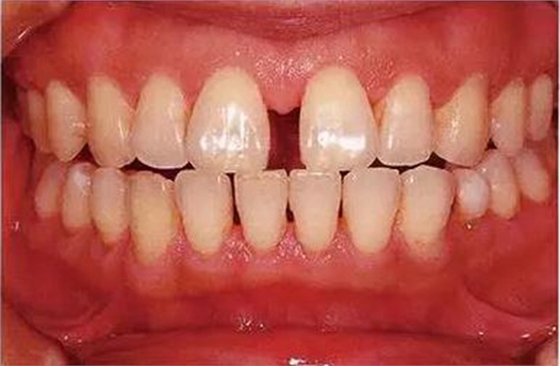

●參考病例① 35歲女性

35歲女性。妊娠4個(gè)月。過去雖然接受過刷牙指導(dǎo),但菌斑控制狀態(tài)依然不理想?;颊哂邪l(fā)現(xiàn)自己刷牙時(shí)牙齦出血。

●參考病例② 25歲女性

25歲女性。菌斑控制狀態(tài)不好。齦溝除磨牙處外全在3mm以下,X光照片上左上、右下、左下的第一磨牙上有垂直性骨吸收。這個(gè)病例是參考病例①10年前的狀態(tài),是典型的侵襲性牙周炎局部型。